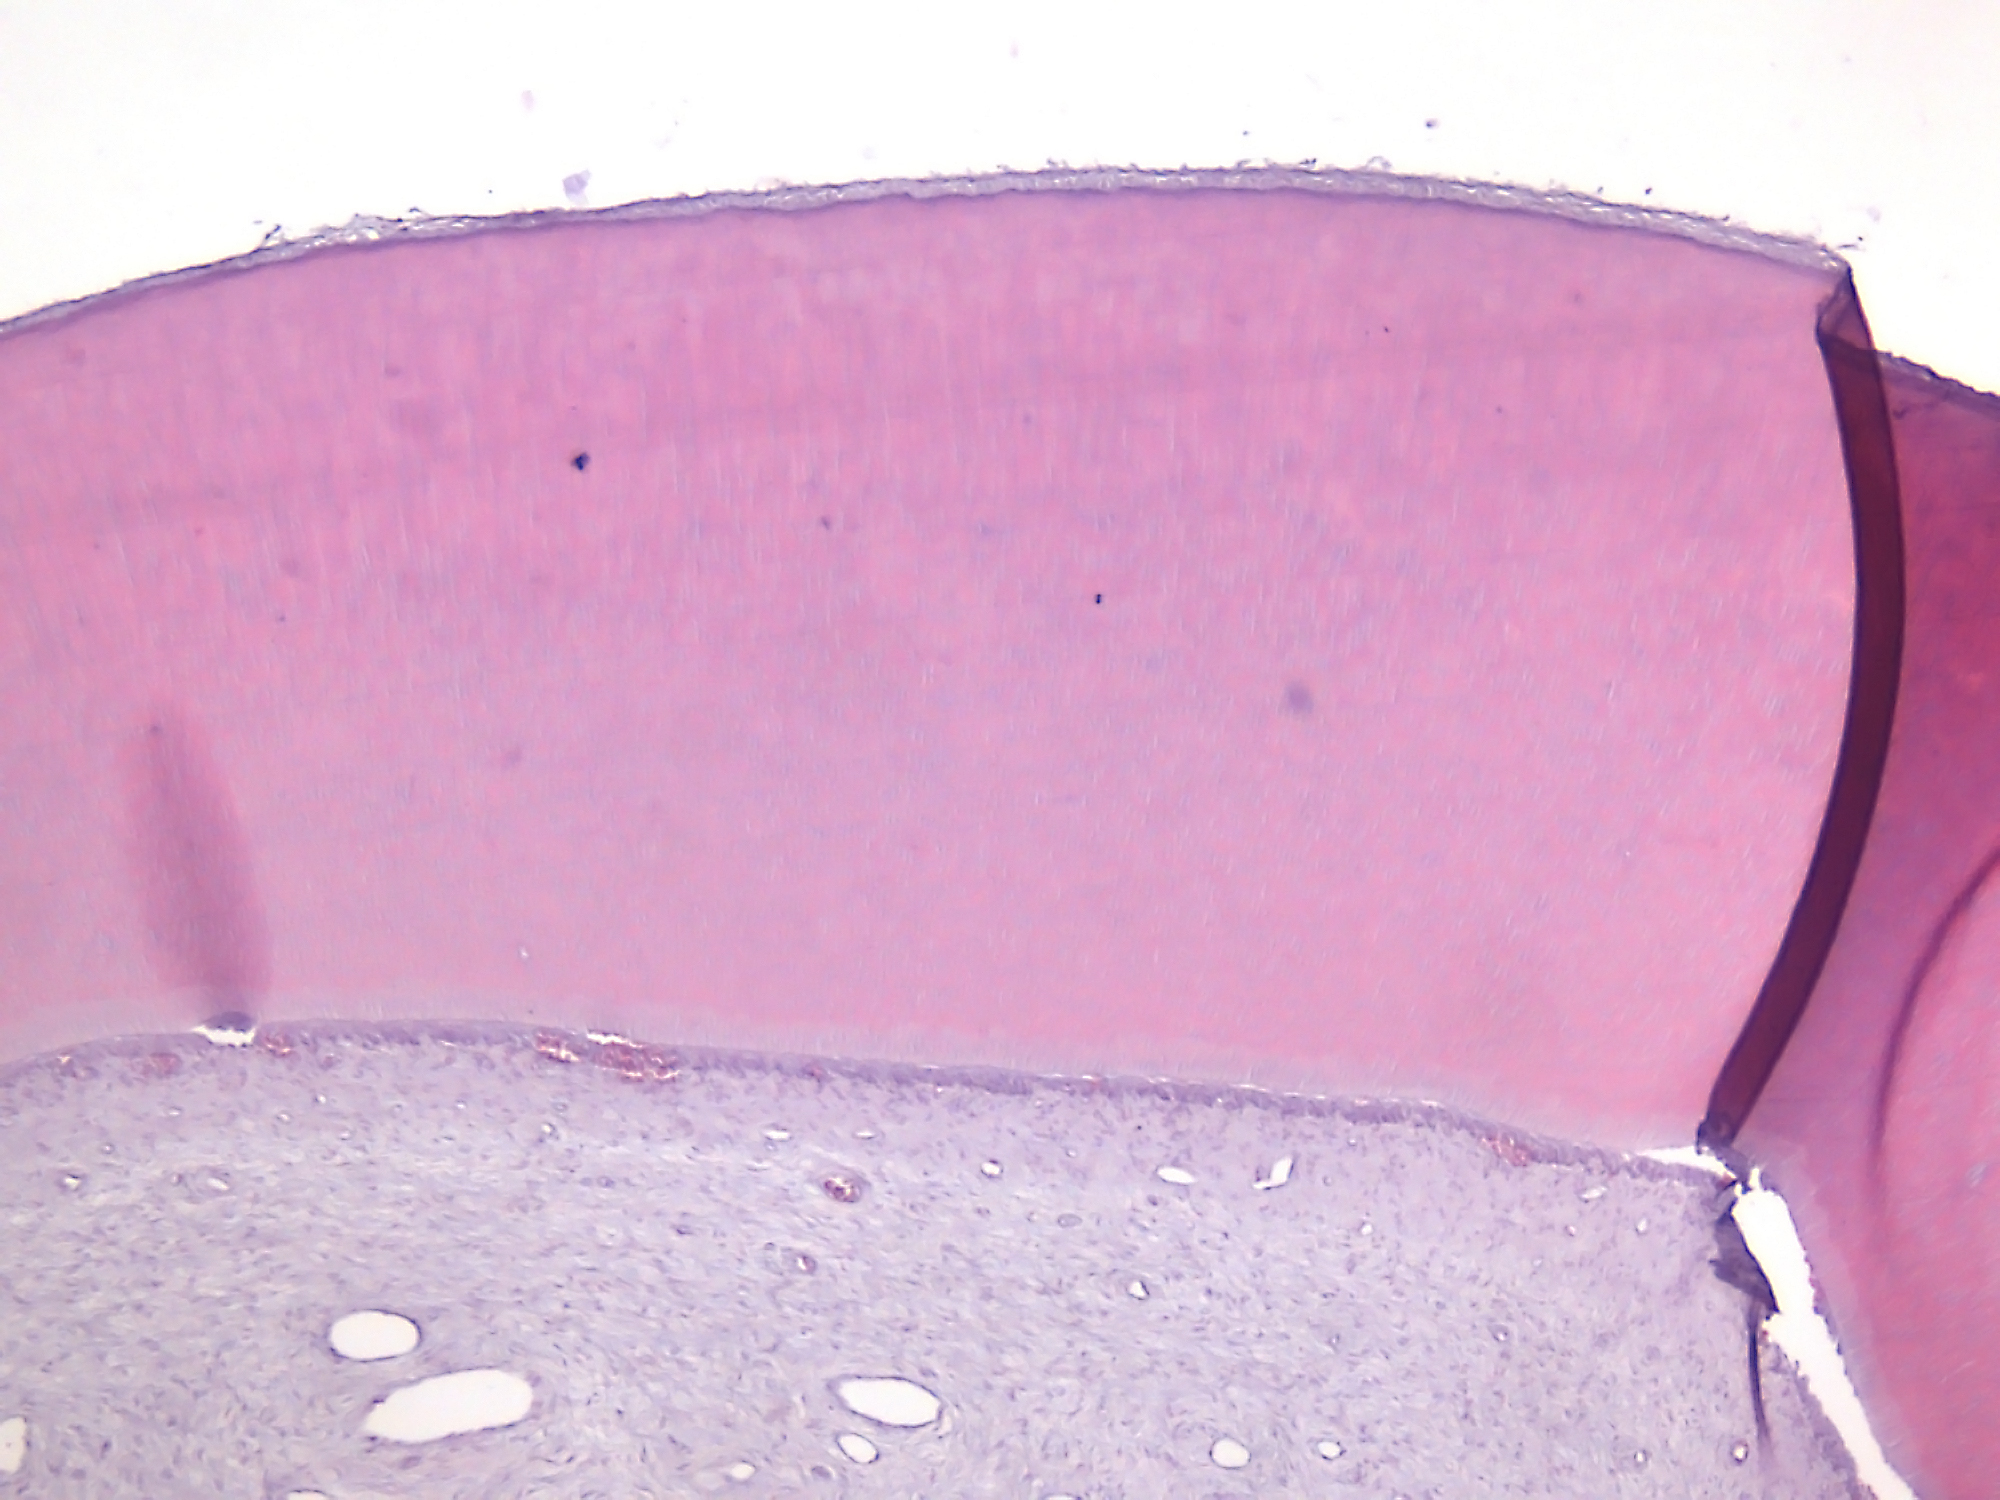

El laboratorio de histotecnología está especializado en el procesamiento histológico de muestras de tejidos blandos y/o de tejidos duros, mineralizados, permitiendo su análisis mediante microscopía óptica para fines de estudio, docencia e investigación. Se reciben muestras de consultorios externos y de servicios de nuestra institución para su diagnóstico anatomopatológico.

● Desparafinización y tinciones histológicas de rutina, como H/E, y tinciones especiales, como tricrómicos, PAS, AB, ATO y rojo alizarina.

● Decalcificación de tejidos mediante soluciones químicas o quelantes (como EDTA).

● Técnicas especiales como citología exfoliativa, transparentación de dientes, desgaste de tejidos duros.